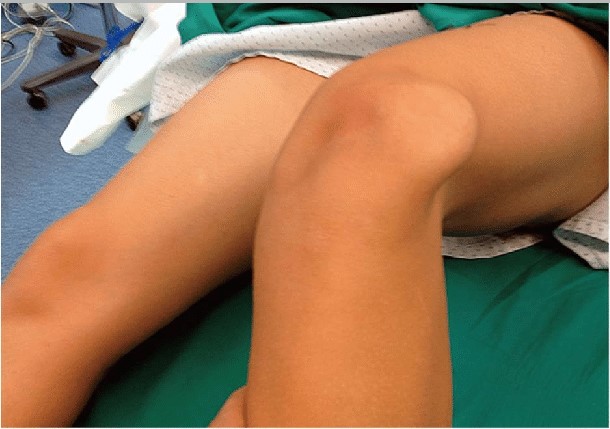

Expand your clinical knowledge with WikiSM.org —a comprehensive resource for sports medicine, MSK exams, and rehabilitation—and MedEdCases.com for real-world, case-based emergency medicine learning